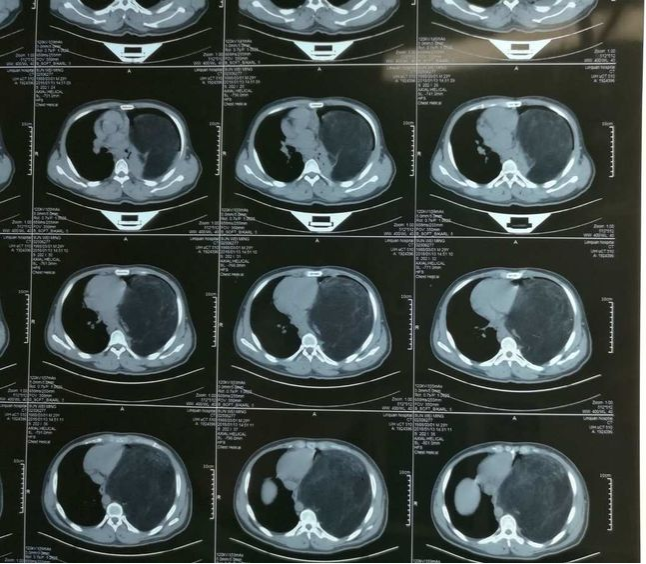

7.胸部肿瘤

3. 电视胸腔镜微创治疗肺吸虫性脓胸

2. 肺吸虫感染性胸膜炎